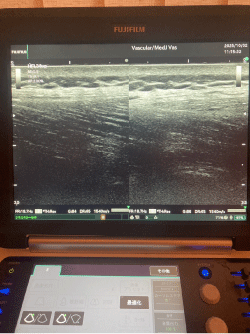

エコー(超音波画像診断装置)は、体内の筋肉・腱・靭帯・血管・神経などの状態をリアルタイムで観察できる非侵襲的な医療機器です。放射線被ばくの心配もなく、安全に繰り返し使用できるのが特徴です。

- 血管の状態:浮腫や血流障害の原因となる血管の狭窄・うっ滞の評価